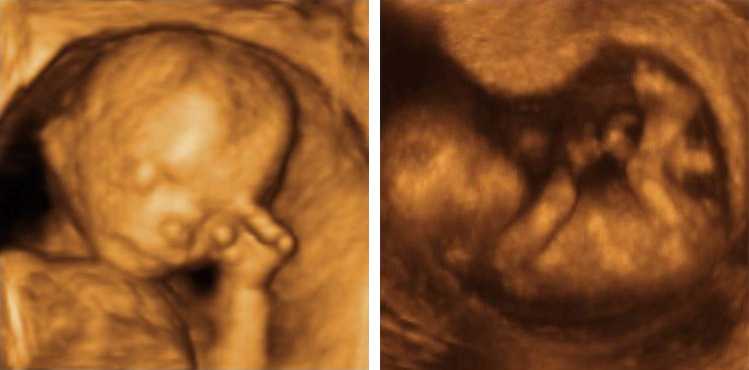

SALEM, Mass. — The Satanic Temple, an organization that identifies as non-theistic and says that it views Satan as a metaphor, has released a statement remarking that Tuesday’s Supreme Court ruling upholding an Indiana law that requires the burial or cremation of aborted babies violates its religious beliefs and its members “may refuse to adhere.” “The Satanic…